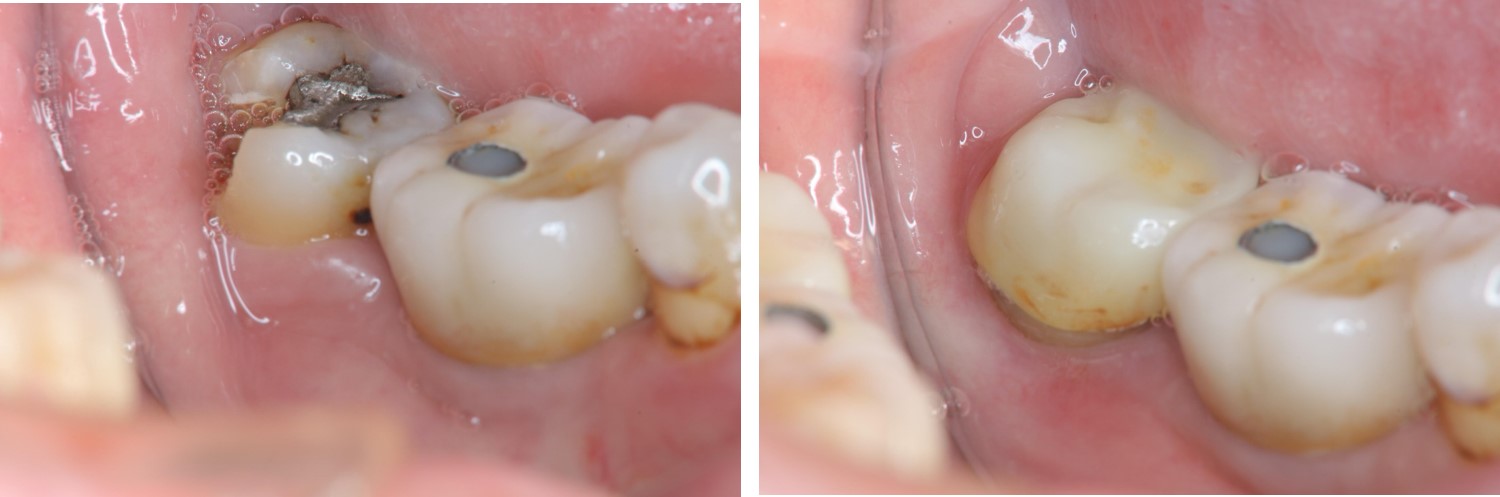

水雷射牙冠增長手術

膺復前評估牙齦、牙齒狀態